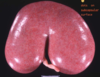

horseshoe kidney

solitary renal cyst

multiple renal cysts

PKD